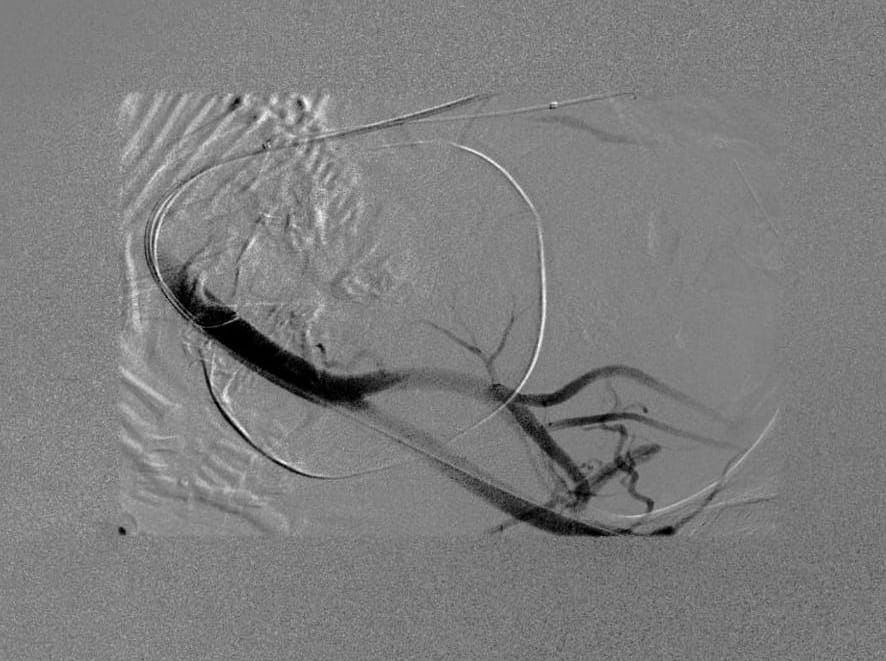

على إثر ذلك استدعى التنسيق الطبي مع فريق الأشعة التداخلية و تعاون فريق أمراض النساء و التوليد للتدخل السريع لإجراء عملية نوعية دقيقة أستغرقت 4 ساعات لإستخراج الجنين و التعامل مع المشيمة الملتصقة بجدار الرحم بدلاً من الجراحة التقليدية لمثل هذه الحالات و التي تعرض المريضة إلى مضاعفات عالية الخطورة تتعلق بالنزيف قد تؤدي إلى الوفاة - لا سمح الله - ، حيث تمكن الفريقان الطبيان من إقفال الشريان الحرقفي الغائر المغذي للأعضاء الداخلية للحوض بواسطة بالون عن طريق الأشعة التداخلية لتقليل النزيف المتوقع من العملية جراء استئصال للرحم مع المشيمة المنغرسة مع استخدام أقل جرعة ممكنة من الأشعة و ولادة الطفل بصحة جيدة و قد تكللت العملية بالنجاح التام ، و بفضل من الله تم بعدها نقل الأم و مولودها تحت الملاحظة الطبية و الرعاية الصحية للاطمئنان عليهما ، حيث غادرا المجمع الطبي و هم يتمتعون بصحة و عافية و لله الحمد .